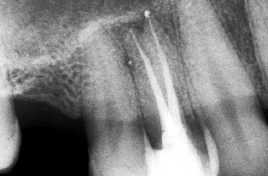

7-

Conometria:

Consiste en introducir un cono

maestro del tamaño a la ultima lima usada, para observar

el ajuste al conducto en la región apical. El cono debe

quedar a 0,5 mm del limite radiográfico apical.

Nota: Los cono que adquirimos

en el comercio suelen no estar estandarizados y por ello

no suelen ajustar en la zona apical. Hoy en el mercado

hay conos con conicidades especiales que están

estandarizados y por lo general suelen ajustar muy bien

en la región apical; pero las limas que debe utilizar

también tienen una conicidad especial. Ver

Protaper Universal

Mtwo

8- Postopertorio inmediato:

Para observar si hay

sobre-obturación, debe entenderse a la sobre-obturación

como el pasaje del cemento sellador por el foramen

apical. Si en el proceso de condensación se observa el

pasaje del extremo del cono de gutapercha hablamos de

una sobre instrumentación.

Nota: las sobreo-bturación con

el cemento sellador suelen ocurrir por el proceso normal

de conformación del conducto, por esto nosotros

utilizamos la técnica

Step

back, para conformar un asiento apical, para evitar

la sobre-instrumentación.